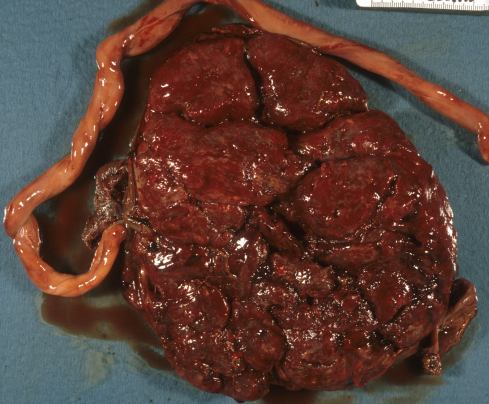

Fig 6c The placental and membrane surfaces are stained with brown hemosiderin. There is an old marginal hematoma from which hemoglobin must have diffused into the amniotic cavity. On the right side is an old (pale) Breus mole (*). The placenta was diagnosed prenatally as placenta previa in a 24 week-gestation fetus with 24 hours of postmortem intrauterine retention. The mother was delivered by Cesarean section.

Fig 28c: The placental and membrane surfaces are stained with brown hemosiderin. There is an old marginal hematoma from which hemoglobin must have diffused into the amniotic cavity. On the right side is an old (pale) Breus mole (*). The placenta was diagnosed prenatally as placenta previa in a 24 week-gestation fetus with 24 hours of postmortem intrauterine retention. The mother was delivered by Cesarean section.